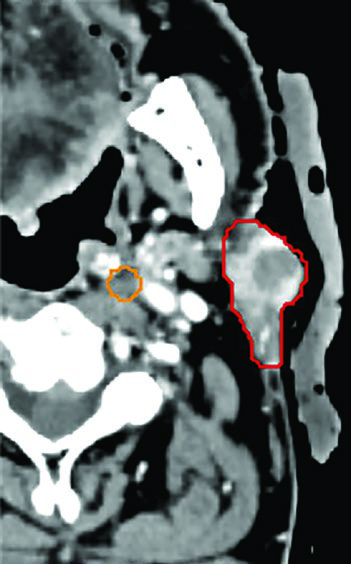

Oligometastatic disease adjacent to brachial plexus. A 55-year-old woman with an unresectable solitary colorectal metastasis to the supraclavicular fossa. The 6-cm node was treated with 45 Gy in 5 fractions, twice weekly. The radiation plan was created with MRI simulation to differentiate the GTV (red) from the brachial plexus (blue) — a crucial differentiation that would be impossible on CT alone given the similar densities of these structures. The mass recurred 3 years later in the left neck.